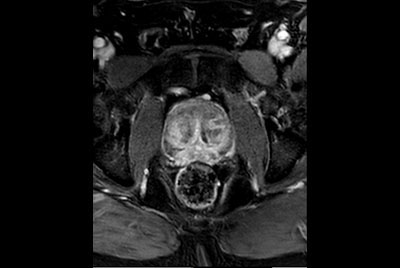

Prostate with dual coil set-up